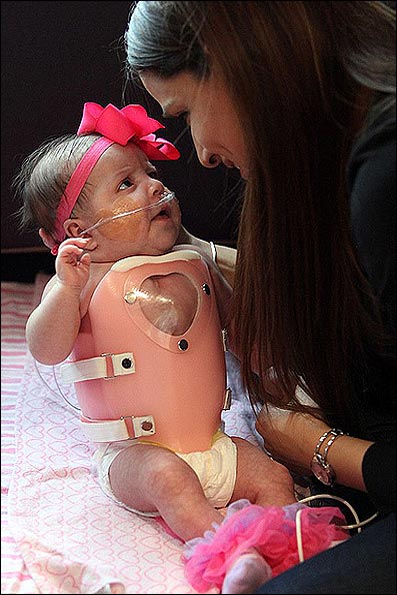

پزشکان این نوزاد را همراه یک محافظه شبیه به زره روی سینه اش مرخص کردند که برای محافظت از قلبش درحین رشد تعبیه شده است. در چند سال آینده وی تحت یک عمل جراحی قرار گرفت تا یک محافظ دائمی داخل دیواره های سینه اش قرار گیرد.

چند هفته پس از آن که پزشکان اعلام کردند این نوزاد دیگر در خطر نیست، اجازه مرخصی وی صادر شد، اما وی به جراحی های دیگری هم در سالهای آینده نیاز دارد تا نقص قلب وی ترمیم شود. این درحالی است که وی باید قدرت خود را به دست آورد تا انجام جراحی های آینده تسهیل شوند.

آدرینا باید تا آخر عمر خود تحت مراقب یک متخصص قلب باقی بمانند اما پزشکان تاکنون از وضعیت وی رضایت دارند. چرا که وی به هیچ نوع سندروم یا شرایط ژنتیکی دیگری که مشکلات قلبیش را تهدید کند مبتلا نیست.